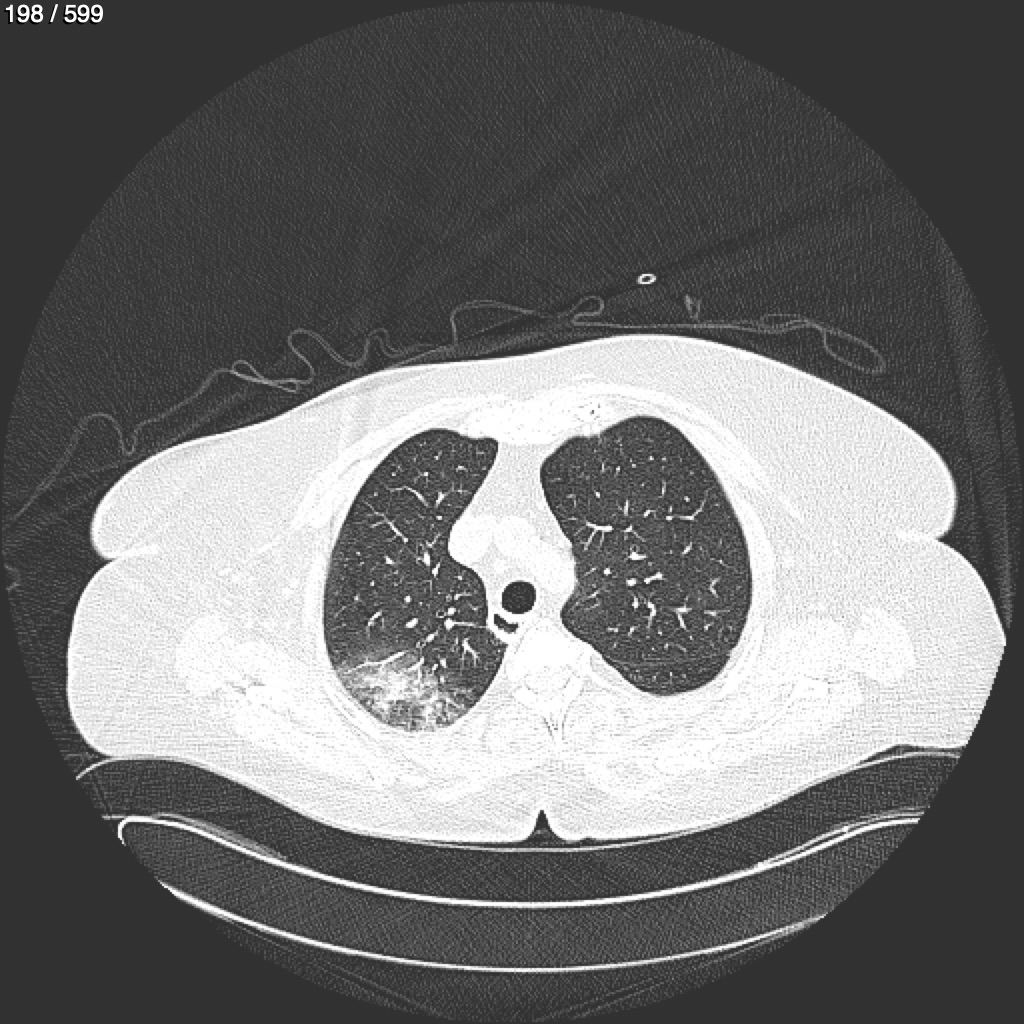

Home G​l​o​r​i​a​ ​G​l​a​d​y​s​ ​B​e​a​s​l​e​y​ ​-​ ​T​ó​r​a​x​ ​T​o​r​a​x​_​S​i​m​p​l​e​ ​(​A​d​u​l​t​o​)